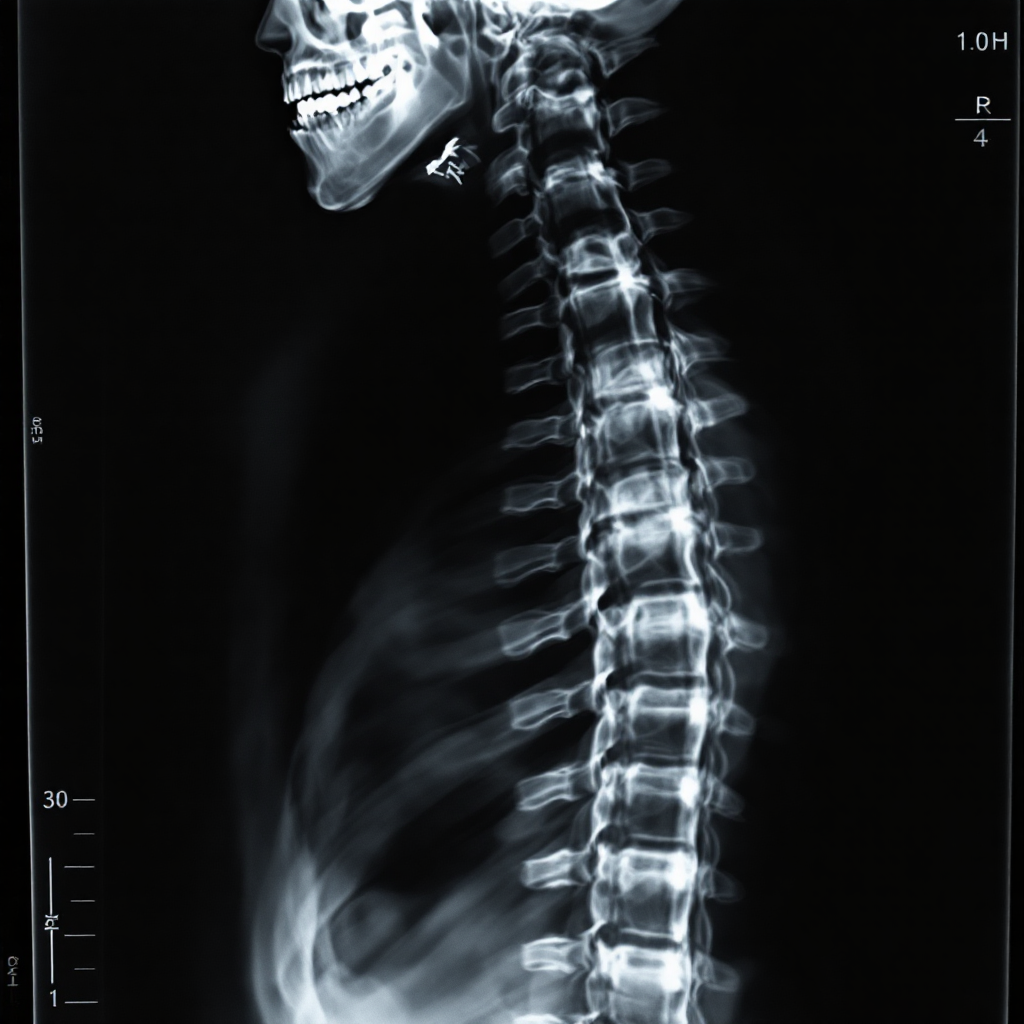

척추측만증을 정확하게 평가하려면 단순 육안 검사만으로는 한계가 있어요. 그래서 대부분의 병원에서는 진단과 추적을 위해 정기적인 영상 촬영을 진행해요. 특히 X-ray는 척추의 곡률을 수치화하고, 변화 여부를 파악하는 데 필수적인 도구죠.

영상 촬영은 일반적으로 전후면 X-ray를 기본으로 해요. 이때 가장 중요한 측정치는 '코브각(Cobb angle)'인데요, 척추의 가장 많이 휘어진 부분을 기준으로 위와 아래의 경사각을 재서 계산하는 방법이에요. 이 수치는 척추측만증의 심각도를 정량적으로 표현해주는 핵심 자료랍니다.

또한, MRI나 CT 촬영도 보조적으로 활용돼요. 특히 신경 눌림이 의심될 경우나, 구조적 이상(척추 분리증, 디스크 등)이 동반된 경우에는 MRI가 더 정밀한 정보를 줄 수 있어요. CT는 뼈 구조를 정밀하게 보여주기 때문에 수술 계획을 세울 때 중요하죠.

정기 촬영을 통해 의료진은 측만증의 진행 속도와 패턴을 모니터링할 수 있어요. 예를 들어, 6개월 간격으로 코브각이 5도 이상 증가한다면 진행형으로 판단하고, 치료 방침을 적극적으로 바꿔야 해요.

영상 자료는 환자 본인과 보호자가 현재 상태를 이해하는 데도 큰 도움이 돼요. 말로만 듣는 것보다 눈으로 보는 것이 훨씬 직관적이거든요. 그래서 병원에서는 촬영 자료를 바탕으로 치료 방향을 설명하고 상담하는 경우가 많아요.